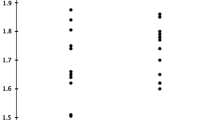

Figure 1 summarizes the results of the cardiovascular autonomic function tests. The BRS was lower in the high VFA group than in the normal VFA group (high VFA group, 8.4 ± 4.2 vs normal VFA group, 12.0 ± 5.1 ms/mmHg, p = 0.0141; Fig. 1a). The plasma norepinephrine concentration was similar in both groups (high VFA group, 242 ± 83 pg/ml; normal VFA group, 207 ± 65 pg/ml; p=ns; Fig. 1b). Furthermore, analysis of HRV in the high and normal VFA groups revealed that the HF power (3.4 ± 1.0 and 3.9 ± 1.2 ln-ms2, respectively; p=ns) and the LF/HF ratios (1.2 ± 0.7 and 1.4 ± 1.1, respectively; p=ns, Fig. 1c) were not significantly different between the two groups. Cardiac 123I-MIBG scintigraphy disclosed that the H/M ratios at early and delayed phases in the high VFA group were significantly smaller than those in the normal VFA group (early phase: 2.03 ± 0.15 vs 2.25 ± 0.27, respectively; p = 0.0021; delayed phase: 1.88 ± 0.18 vs 2.20 ± 0.21, respectively, p < 0.0001; Fig. 1d). The percent WR of 123I-MIBG was higher in the high VFA group than in the normal VFA group (44.8 ± 8.5% vs 35.7 ± 7.6%, p = 0.0005; Fig. 1d).

Comparison of autonomic function tests of type 2 diabetes mellitus patients with normal visceral fat accumulation (normal VFA) or high visceral fat accumulation (high VFA). a Baroreflex sensitivity (BRS). b Plasma norepinephrine (NE) concentration. c Heart rate variability (HRV). Power of the high-frequency component (HF, 0.15–0.40 Hz; a) and the ratio of the low-frequency power (LF; 0.04 to 0.15 Hz) to HF power (LF/HF, b). The distribution of HRV values was skewed and the values were thus transformed to natural logarithmic values. d Cardiac 123I-MIBG scintigraphic findings. Myocardial uptake of 123I-MIBG during the early (a) and delayed (b) phases. Myocardial uptake of 123I-MIBG is expressed as the mean heart-to-mediastinum (H/M) ratio. c Percent washout rate (WR) of 123I-MIBG. Data are mean±SD. ns not significant